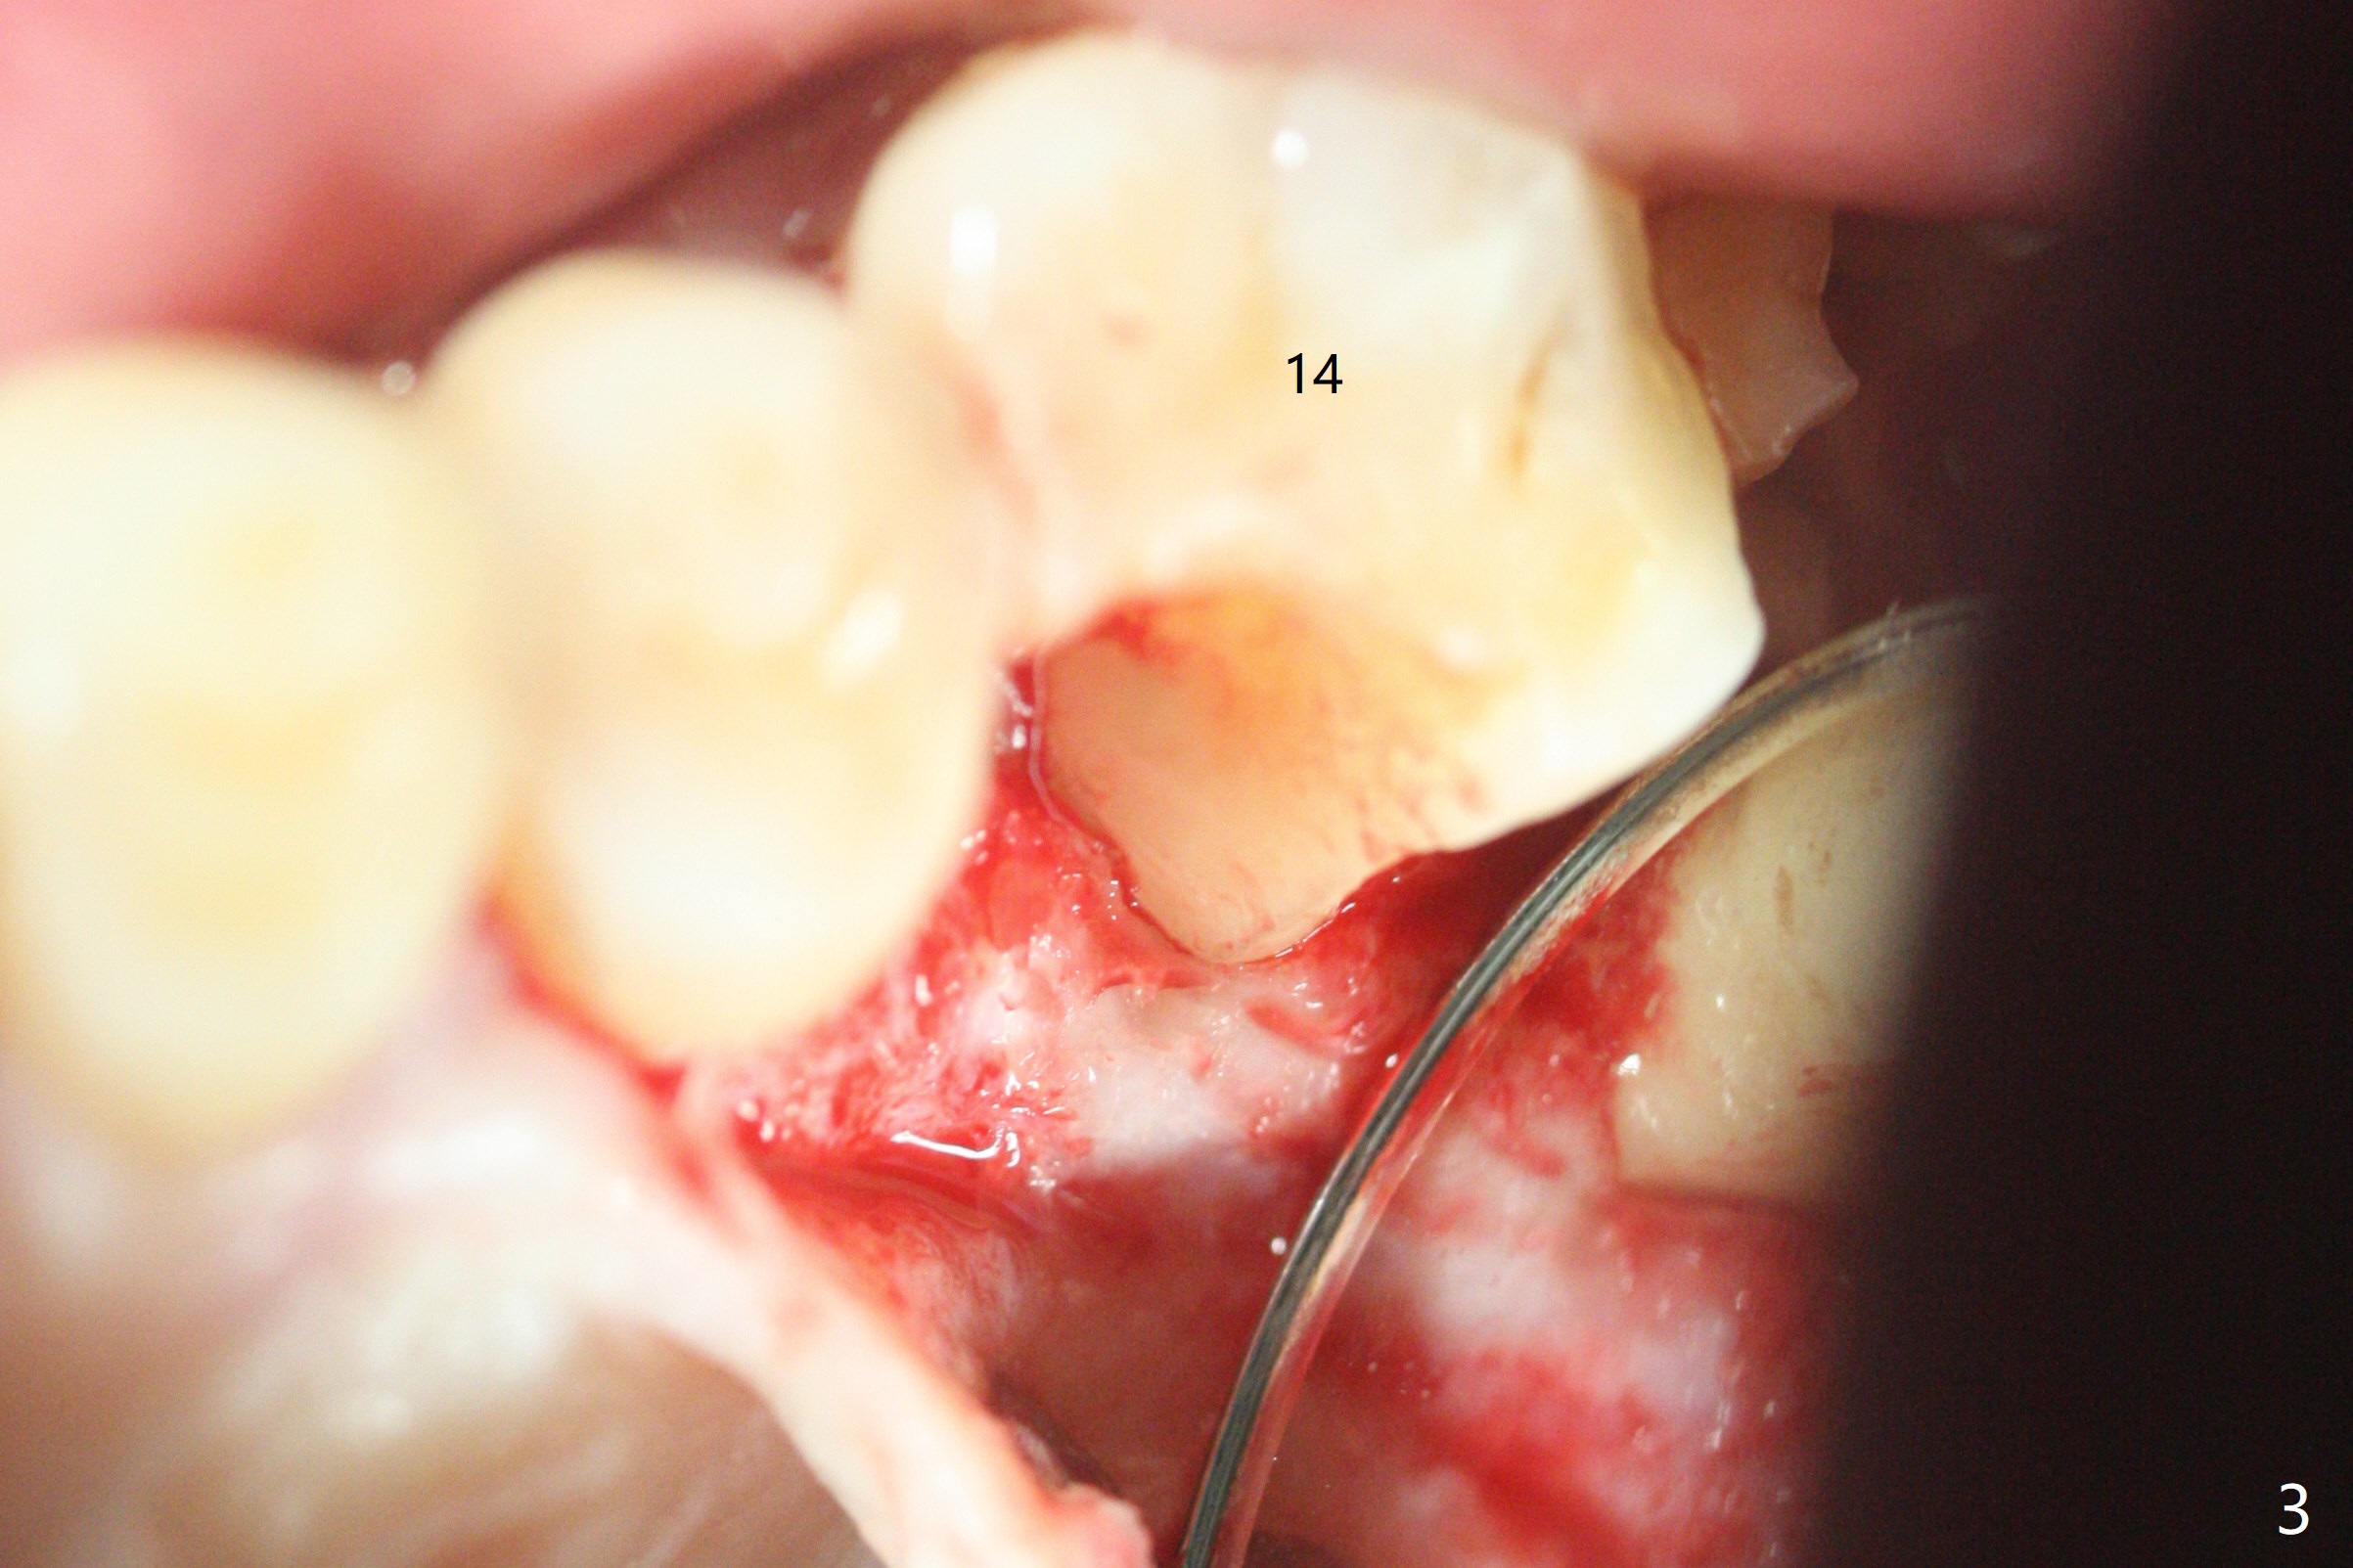

A 47-year-old man has pain at #2 and 15, while #14 has mesiolingual subgingival fracture (Fig.1). #2 is deemed non-salvageable by an endodontist, whereas RCT is finished at #15. When the patient returns for restoration, he reports that the filling is out at #15. In fact it has subcrestal fracture (Fig.2), while #14 equicrestal and difficult to restore (Fig.3). Although the patient agrees to have implants at #2 and 15, DB bone loss at #2 makes it difficult for implant (Fig.4). Use FC implant for primary stability. Insert a small piece of cotton pellet or healing screw and pack sticky bone around the implant before placing a temporary abutment. The latter will form a large gingival cuff, which makes it easy to place pair abutment without interference from the crestal bone. Screw loosening will be reduced. In fact there is PARL of the palatal root of #14 (Fig.5). A FC implant will be also placed at #15 for the same reason (Fig.6).